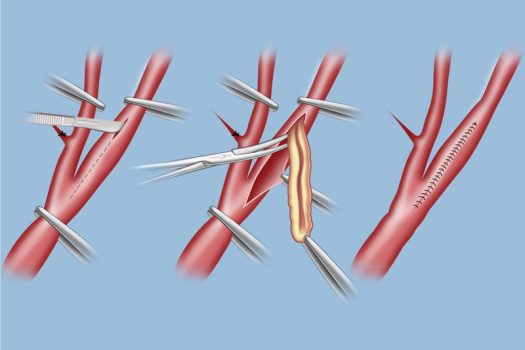

- Ενδαρτηρεκτομή

Σύμφωνα με διεθνείς μελέτες και τις σύγχρονες κατευθυντήριες οδηγίες φαίνεται ότι στις περισσότερες των περιπτώσεων λιγότερο επικίνδυνο είναι το χειρουργείο ενδαρτηρεκτομής. Βέβαια στη φαρέτρα του αγγειοχειρουργου, υπάρχει και η αποκατάσταση με στεντ αφού κάθε ασθενής έχει την ιδιαιτερότητα του.Ο διεγχειρητικός κίνδυνος εγκεφαλικού ή θανάτου είναι 1.5% για την ενδαρτηρεκτομή και 2% για το στεντ σε ασυμπτωματική νόσο. Η αντιμετώπιση της νόσου μπορεί να είναι συντηρητική στα αρχικά στάδια, με ρύθμιση των παραγόντων κινδύνου και παρακολούθηση, ενώ στα τελικά στάδια η αντιμετώπιση πρέπει να είναι χειρουργική. Υπάρχει σε επιλεγμένες περιπτώσεις και η ενδαγγειακή προσέγγιση, με τοποθέτηση ενδονάρθηκα μέσα στην καρωτίδα.

Στένωση δεξιάς Καρωτίδας ΣΥΜΦΩΝΑ ΜΕ ΔΙΕΘΝΕΙΣ ΜΕΛΕΤΕΣ ΚΑΙ ΤΙΣ ΣΥΓΧΡΟΝΕΣ ΚΑΤΕΥΘΥΝΤΗΡΙΕΣ ΟΔΗΓΙΕΣ ΦΑΙΝΕΤΑΙ ΟΤΙ ΣΤΙΣ ΠΕΡΙΣΣΟΤΕΡΕΣ ΤΩΝ ΠΕΡΙΠΤΩΣΕΩΝ ΛΙΓΟΤΕΡΟ ΕΠΙΚΙΝΔΥΝΟ ΕΙΝΑΙ ΤΟ ΧΕΙΡΟΥΡΓΕΙΟ ΕΝΔΑΡΤΗΡΕΚΤΟΜΗΣ. ΣΕ ΚΑΘΕ ΠΕΡΙΠΤΩΣΗ ΣΤΗ ΦΑΡΕΤΡΑ ΤΟΥ ΑΓΓΕΙΟΧΕΙΡΟΥΡΓΟΥ, ΥΠΑΡΧΕΙ ΚΑΙ Η ΑΠΟΚΑΤΑΣΤΑΣΗ ΜΕ ΣΤΕΝΤ ΑΦΟΥ ΚΑΘΕ ΑΣΘΕΝΗΣ ΕΧΕΙ ΤΗΝ ΙΔΙΑΙΤΕΡΟΤΗΤΑ ΤΟΥ.

ΠΟΣΟ ΔΙΑΡΚΕΙ ΤΟ ΧΕΙΡΟΥΡΓΕΙΟ;

Περίπου 2 ώρες. Ο ασθενής επιστρέφει στο κρεβάτι του και σε δύο μέρες παίρνει εξιτήριο. Η τομή στον λαιμό κλείνει με ειδικά ράμματα και γίνεται πλαστική αποκατάσταση με άριστα αισθητικά αποτελέσματα.

Χειρουργική Αποκατάσταση Καρωτιδικής Νόσου